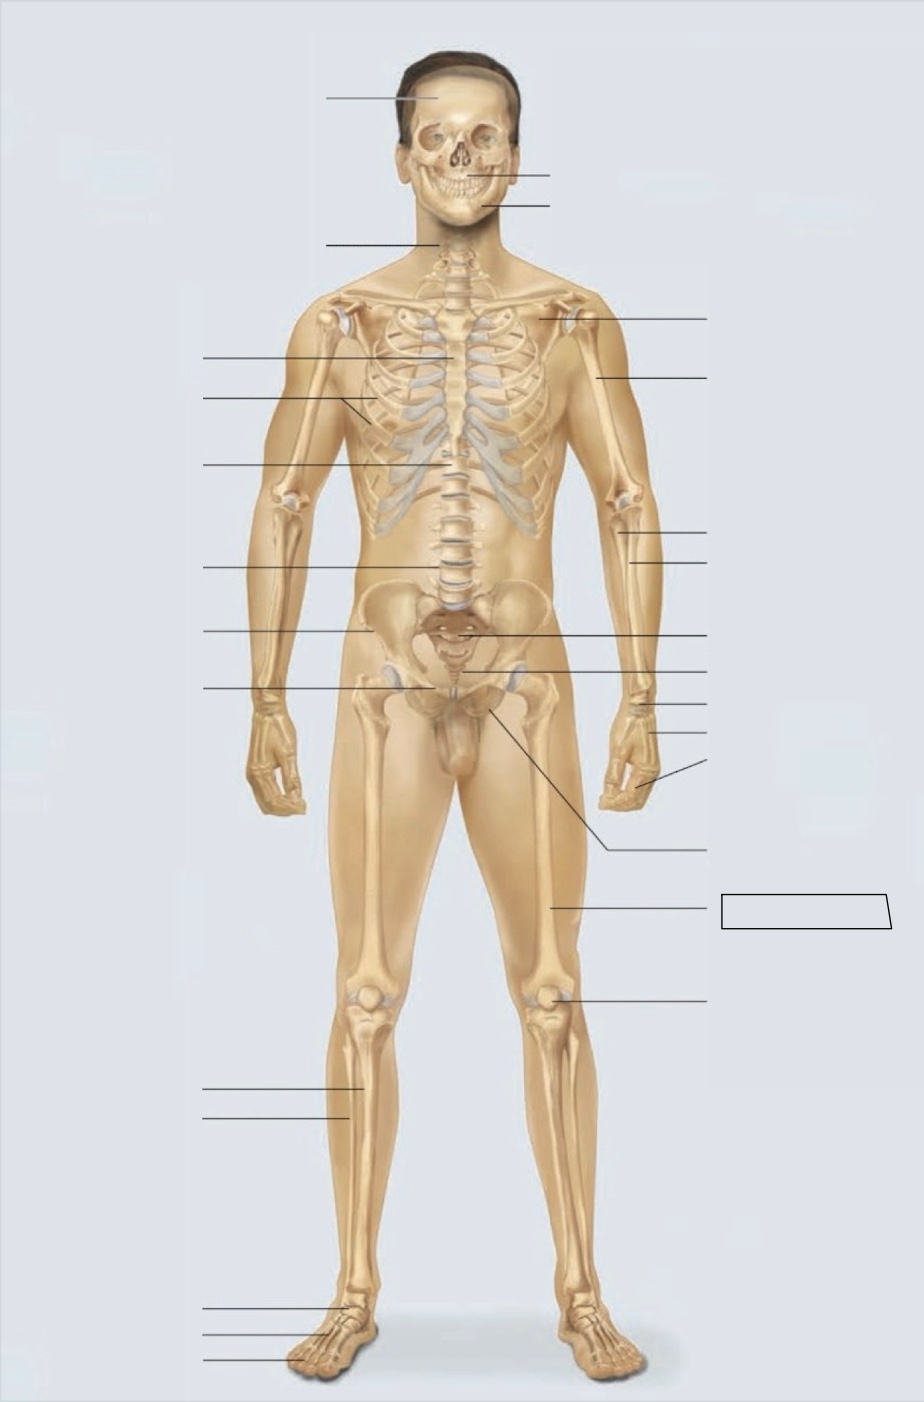

maxilla

mandible

scapula

humerus

ulna

radius

sacrum

coccyx

carpals

metacarpals

phalanges

ischium

femur

patella

phalanges

metatarsals

tarsals

fibula

tibia

pubis

ilium

lumbar vertebrae (L4)

thoracic vertebrae (T11)

ribs

sternum

cervical vertebrae

skull